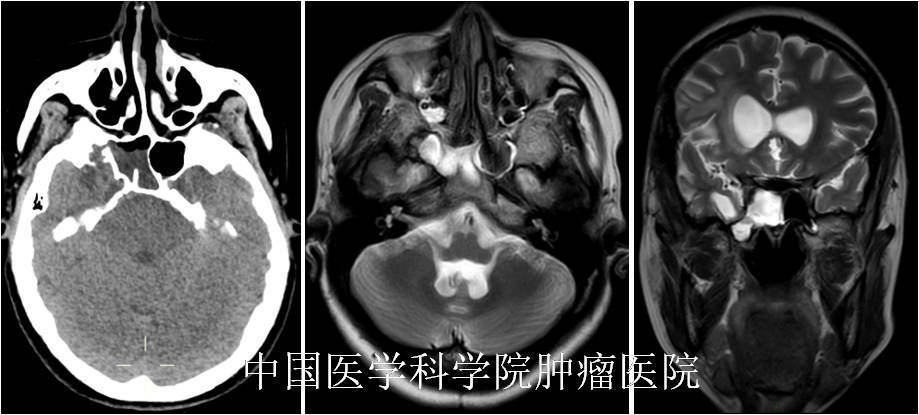

內(nèi)鏡經(jīng)鼻手術(shù)修補(bǔ)腦脊液鼻漏,挽救患者生命

摘要:因鼻子流水就醫(yī)的中年女性,檢查后發(fā)現(xiàn)是顱底腦膜腦膨出、繼發(fā)腦脊液鼻漏?;颊弑乔涣魉黠@、喘氣費(fèi)力,而且腦脊液鼻漏極易誘發(fā)顱內(nèi)感染、甚至危及生命。但幸而就醫(yī)還算及時(shí),我們通過經(jīng)鼻蝶內(nèi)鏡手術(shù)成功修補(bǔ)了顱底,挽救了患者的生命、改善了患者的生存質(zhì)量。在此叮囑大家:平時(shí)有類似鼻子流水、持久不愈等類似問題,一定要到??凭驮\評(píng)估、排除相關(guān)疾病風(fēng)險(xiǎn),不要盲目對(duì)癥處理,延誤病情?!净拘畔ⅰ颗?,46歲【疾病類型】腦脊液鼻漏【就診醫(yī)院】中國(guó)醫(yī)學(xué)科學(xué)院腫瘤醫(yī)院【就診時(shí)間】2021-3【治療方案】全麻下行內(nèi)鏡下經(jīng)鼻蝶-上頜竇-翼突入路-右側(cè)中顱底前內(nèi)側(cè)腦膜腦膨出、腦脊液鼻漏修補(bǔ)術(shù)?!局委熤芷凇孔≡?0天,每半年門診隨訪。【治療效果】術(shù)后患者腦脊液鼻漏消失,呼吸順暢。一、初次面診???患者自訴“鼻腔流水半年、加重3個(gè)月”,初來門診時(shí)一般情況挺好的,但需要不斷擦拭鼻腔流出的液體。經(jīng)過問診了解到:患者半年前出現(xiàn)鼻腔流清水,近3個(gè)月癥狀加重,低頭時(shí)明顯,自覺喘氣費(fèi)力,無頭痛、發(fā)熱癥狀。于當(dāng)?shù)蒯t(yī)院就診、行頭顱CT:提示自發(fā)性腦脊液鼻漏可能;當(dāng)?shù)蒯t(yī)生說手術(shù)復(fù)雜、風(fēng)險(xiǎn)較大,建議轉(zhuǎn)院治療。這時(shí)患者內(nèi)心充滿了恐懼,意識(shí)到病情較嚴(yán)重,于是來到我院就診,尋求進(jìn)一步治療。二、治療經(jīng)過???患者來院時(shí)一般情況可,院查體:神清,精神可,言語流利,高級(jí)智能檢查正常。嗅覺粗測(cè)正常。雙眼視力、視野粗測(cè)正常。雙眼各向運(yùn)動(dòng)充分。雙瞳孔等大等圓,直徑3mm,光反射存在。雙側(cè)面部針刺覺對(duì)稱。眼瞼無下垂,雙側(cè)額紋、鼻唇溝對(duì)稱正常。鼻腔持續(xù)流出清亮液體。雙耳聽力粗測(cè)正常。懸雍垂居中,雙側(cè)軟腭抬舉對(duì)稱。雙側(cè)咽反射靈敏。轉(zhuǎn)頸、抬頭有力,聳肩有力。伸舌居中。四肢肌張力不高,肌力正常。病理征(-)。頸軟,腦膜刺激征(-)。為了進(jìn)一步明確病變部位和性質(zhì),進(jìn)行頭顱CT和MRI檢查,結(jié)果提示:右側(cè)中顱底前內(nèi)側(cè)腦膜腦膨出,局部骨質(zhì)不連續(xù),腦組織向外膨出至右側(cè)蝶竇側(cè)隱窩下外側(cè),右側(cè)腦室顳角前部明顯擴(kuò)大、前移,顳極腦組織菲??;右側(cè)蝶竇積液,提示腦脊液鼻漏。根據(jù)病史和臨床癥狀,并結(jié)合頭顱MRI的結(jié)果,初步診斷為自發(fā)性腦脊液鼻漏、右側(cè)中顱底前內(nèi)側(cè)腦膜腦膨出。入院后,醫(yī)護(hù)人員對(duì)患者的心理進(jìn)行疏導(dǎo),獲得患者及其家屬的同意后,完善血常規(guī)、生化、凝血、心電圖等常規(guī)術(shù)前檢查,未見明顯異常,排除手術(shù)禁忌癥。建議患者進(jìn)行手術(shù)、修補(bǔ)顱底,避免顱內(nèi)感染、危及生命。術(shù)前向患者和家屬充分講解了手術(shù)的必要性和手術(shù)相關(guān)的風(fēng)險(xiǎn),征得了患者和家屬的同意和配合。在充分完善術(shù)前相關(guān)準(zhǔn)備工作后,在全麻下進(jìn)行了經(jīng)鼻蝶-上頜竇-翼突入路-右側(cè)中顱底前內(nèi)側(cè)腦膜腦膨出、腦脊液鼻漏修補(bǔ)術(shù),手術(shù)順利,耗時(shí)2小時(shí)?;颊咔逍押蟀卜挡》?。術(shù)后顱底膨出組織標(biāo)本送病理學(xué)檢查。術(shù)后給予患者頭孢呋辛預(yù)防性抗感染治療48小時(shí),并給予止血、止吐、保護(hù)胃粘膜、補(bǔ)液支持等對(duì)癥冶療,患者恢復(fù)順利。三、治療效果術(shù)后病人恢復(fù)良好,體溫正常,術(shù)后第2天下床活動(dòng)、恢復(fù)飲食。查體:神志清楚,言語流利。雙瞳孔等大等圓,直徑約3mm,對(duì)光反射靈敏;眼球各項(xiàng)運(yùn)動(dòng)正常。頸部柔軟、無強(qiáng)直。術(shù)后第7天拔除鼻腔碘仿紗條,鼻腔干燥、無異常滲出,呼吸順暢。術(shù)后第8天順利出院。病理結(jié)果回報(bào):腦組織,伴膠質(zhì)細(xì)胞增生,局部纖維組織增生及炎細(xì)胞浸潤(rùn),符合腦膨出改變。術(shù)后當(dāng)天復(fù)查頭顱CT:提示顱底重建良好。四、注意事項(xiàng)1、手術(shù)前積極配合醫(yī)生調(diào)整身體狀況,保證充足的睡眠。2、術(shù)前配合醫(yī)生完善頭顱CT、MRI等輔助檢查,以明確病變部位和范圍,制定合理的手術(shù)方案。3、術(shù)后做好鼻腔手術(shù)通道的管理,保持大便通暢、避免咳嗽打噴嚏,防止腦脊液漏。4、術(shù)后嚴(yán)格根據(jù)醫(yī)囑用藥,降低術(shù)后發(fā)生顱內(nèi)感染等并發(fā)癥的風(fēng)險(xiǎn)。5、出院后注意休息,注意清淡飲食,均衡營(yíng)養(yǎng),避免過度用眼,保證充足的睡眠。6、出院后注意保暖、保持大便通暢、心情舒暢,避免感冒咳嗽、搬動(dòng)重物、用力大便等動(dòng)作,防止腦脊液漏發(fā)生。7、出院后,如有發(fā)熱、頭痛、惡心、嘔吐等不適癥狀,及時(shí)就近就診。8、3個(gè)月后回院復(fù)查頭顱MRI等。五、個(gè)人感悟??腦脊液鼻漏是腦脊液通過顱底(前、中或后窩)或其他部位骨質(zhì)缺損、破裂處流出的“清鼻涕”,經(jīng)過鼻腔流出體外。不過腦脊液鼻漏與真正的“鼻涕”不盡相同,其主要表現(xiàn)為鼻腔間斷或持續(xù)流出清亮、水樣液體,但沒有鼻涕的粘性,可助患者進(jìn)行初步分辨。??腦脊液鼻漏的病因涉及多個(gè)方面:其中90%以上是創(chuàng)傷性腦脊液漏,而創(chuàng)傷性腦脊液鼻漏又分為外傷性腦脊液鼻漏和醫(yī)源性腦脊液鼻漏兩種;小部分的是自發(fā)性腦脊液鼻漏,可能是先天性顱底發(fā)育不良導(dǎo)致腦膜腦膨出、顱底腫瘤或感染破壞繼發(fā)等等。???病因的多樣也就導(dǎo)致了不同病因患者的臨床變現(xiàn)不同,常見表現(xiàn)除鼻腔間接或持續(xù)流出清亮、水樣液體外,部分患者伴嗅覺減退或者消失,還有一小部分患者會(huì)出現(xiàn)反復(fù)發(fā)作的化膿性腦膜炎(可出現(xiàn)發(fā)熱、頭痛、惡心嘔吐等癥狀)。而外傷性腦脊液鼻漏可同時(shí)有血性液體自鼻孔流出,其痕跡的中心呈紅色而周邊清澈,或鼻孔流出的無色液體干燥后不呈痂狀。??如果腦脊液鼻漏癥狀長(zhǎng)時(shí)間得不到愈合,很容易導(dǎo)致逆行性的感染,引起腦膜炎,導(dǎo)致患者出現(xiàn)明顯的頭痛、頭暈、惡心、嘔吐、發(fā)熱、昏迷等,甚至危及生命。不僅如此,長(zhǎng)時(shí)間腦脊液鼻漏還會(huì)給患者的全身健康都帶來一定的影響,有些患者可能會(huì)出現(xiàn)呼吸困難、精神萎靡、食欲不振等癥狀,最為嚴(yán)重的還可能誘發(fā)低顱壓和顱內(nèi)感染等并發(fā)癥產(chǎn)生,由此可見該疾病的嚴(yán)重性。本例患者是自發(fā)性腦脊液鼻漏,與顱底部位發(fā)育不良導(dǎo)致的腦膜腦膨出有關(guān)。漏口位于蝶竇側(cè)隱窩、中顱底的內(nèi)側(cè),傳統(tǒng)開顱手術(shù)修補(bǔ)困難、對(duì)腦組牽拉損傷大;而內(nèi)鏡經(jīng)鼻蝶-翼突入路,能夠很好的顯露蝶竇側(cè)隱窩的漏口和膨出組織,術(shù)中利用翼腭窩的脂肪和帶蒂鼻中隔粘膜瓣能夠很好的修復(fù)顱底,而且經(jīng)鼻手術(shù)損傷小、恢復(fù)快。在此叮囑大家:平時(shí)有類似鼻子流水、持久不愈等類似問題,一定要到??凭驮\評(píng)估、排除相關(guān)疾病風(fēng)險(xiǎn),不要盲目對(duì)癥處理,延誤病情。